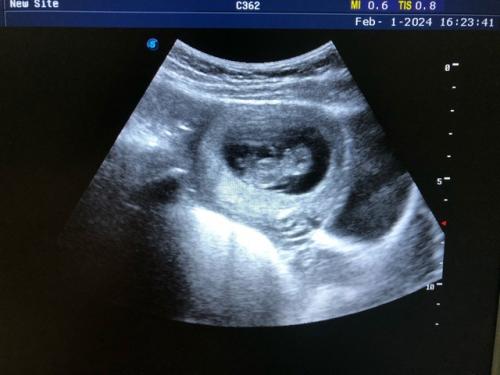

6 3 января почувствовала что со мной что-то не то, решила на работе сделать ради интереса тест на беременность и осталась в приятном шоке! Эти заветные 2 полоски, не верила до последнего. Ждала первое узи.

7 1 февраля впервые вижу своего сына, ему было уже 9 недель и 8 дней моему счастью не было предела.